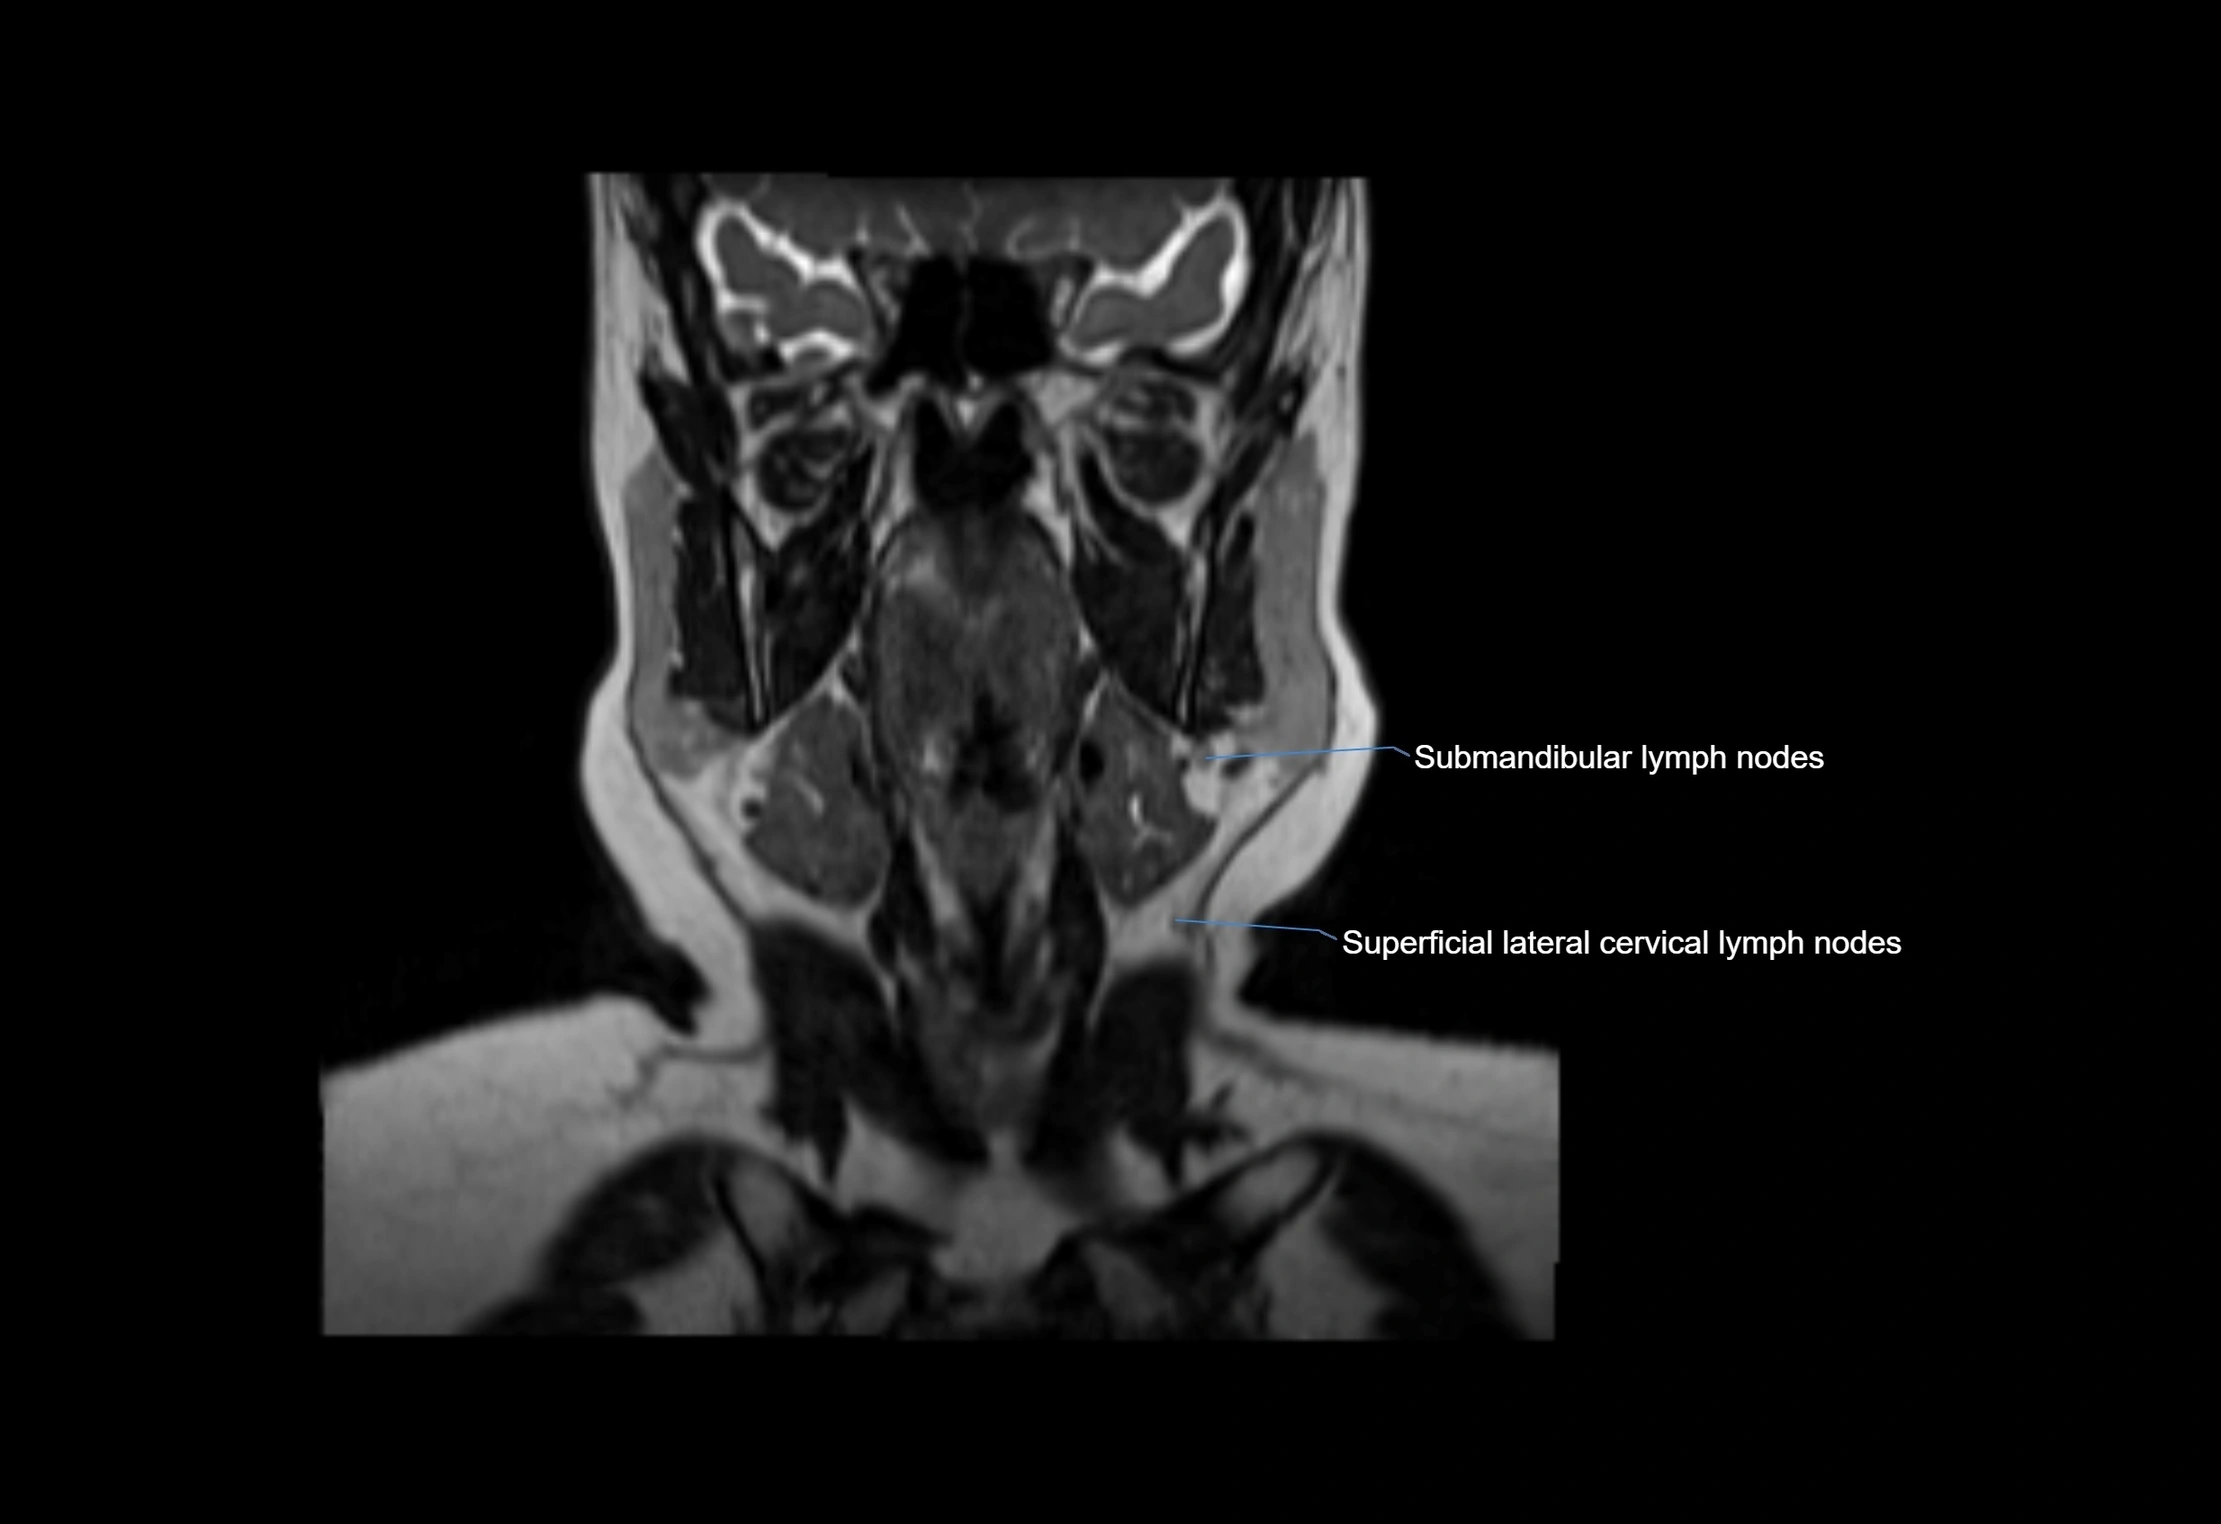

Accessory lymph nodes

Accessory lymph nodes are small, secondary lymph nodes located along the main facial and cervical lymphatic chains, often adjacent to primary lymph nodes, such as preauricular, submandibular, or occipital nodes. They are typically less than 5 mm in diameter, embedded within subcutaneous fat or connective tissue, and may be variable in number and location. These nodes provide additional filtration and immune surveillance for lymph collected from the face, scalp, and neck regions. Accessory lymph nodes are usually non-palpable in healthy individuals but may enlarge in response to infection, inflammation, or metastasis, making them clinically significant.

Location

• Found along primary lymph node chains, including preauricular, submandibular, parotid, and occipital regions

• Embedded in subcutaneous fat or superficial fascia, often lateral or posterior to primary nodes

MRI images

image